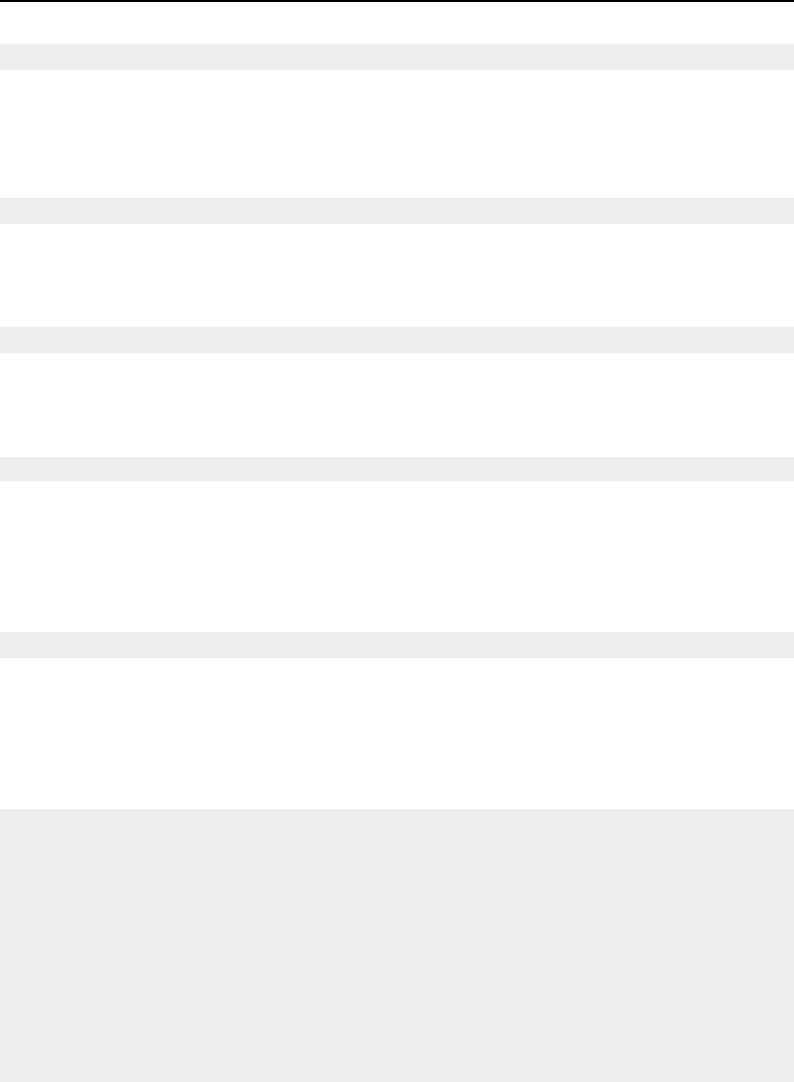

- Center Initialization

- Geometrical Representation